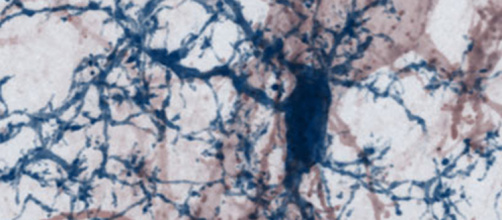

• Publié le 26 janv. 2021

Réparer les synapses pour combattre la sclérose en plaques

comm_presse_merkler_media.jpeg